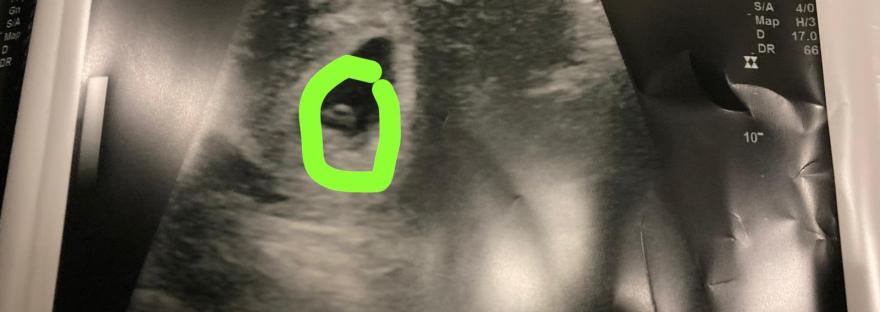

So, you have a positive pregnancy test, now what?!

I've taken a few weeks detour of the "story" of my being pregnant so thought I'd jump back in. Going back to the day after finding out I was pregnant, when I had taken the digital dating test that put me at about five weeks pregnant... Here's the thing though, I now had these three… Continue reading So, you have a positive pregnancy test, now what?!